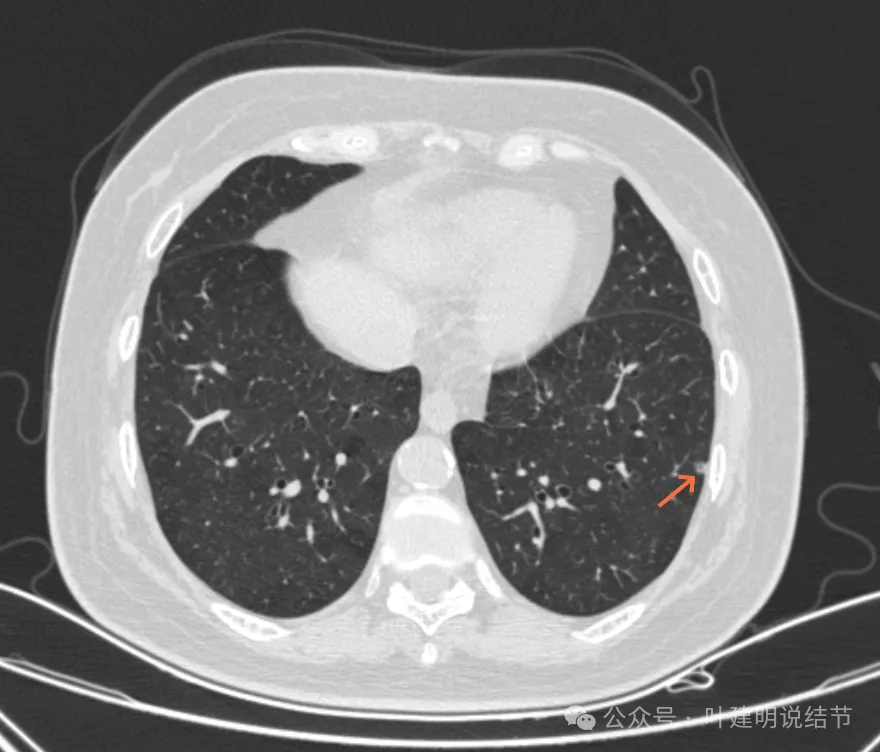

病灶45:左下叶磨玻璃结节,轮廓较清。

病灶46:左下叶磨玻璃结节,轮廓较清,密度稍高,贴着胸膜,轮廓与边界清。

病灶48:左下叶淡磨玻璃结节,轮廓较清,似有小血管征与小空泡征。